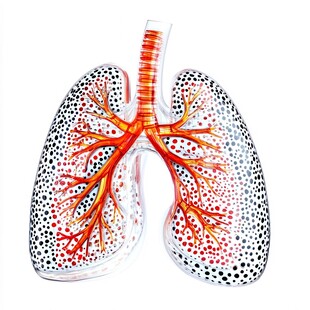

人体肺部解剖图医学插画 商用作品

人体肺部解剖图医学插画 商用作品 -

人体呼吸器官示意图 商用作品

人体呼吸器官示意图 商用作品 -